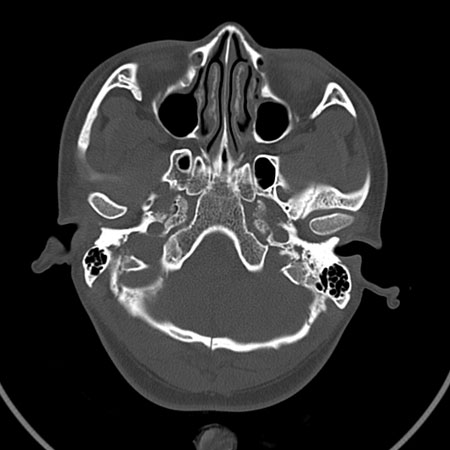

ct 扫描发现枕骨变异一例

温毅,张瑞萍,张延林,尹涛

患者男,19 岁。因头部外伤就诊。体检:营养、发育良好,五官对称,外观无畸形。右额部见局部皮肤青紫,无皮肤破损。ct 扫描:脑组织及颅外软组织未见异常;骨窗见枕骨中下部,由枕骨内、外隆凸至枕骨大孔处有一线样长约27 mm裂隙(图1、2),宽约1 .0 mm。边缘光滑、硬化,贯穿枕骨内外板。颅骨无

凹陷及移位征象。

讨论: 胚胎学研究证实,枕骨发源于脊椎而不是颅骨,在胚胎形成40 ~ 42 体节时,前部5 个体节形成

枕骨。枕骨基底部和鳞部各有一个骨化中心,还有两个枕骨外侧部[1],分别出现于胚胎的第7 周及第8 周。本例枕骨枕鳞部骨缝可能与枕骨各骨化中心发育障碍有关。经枕骨隆凸至枕大孔处骨缝变异极为罕见,易误诊为骨折,细致观察骨缝边缘是否有硬化和软组织是否肿胀即可与骨折相鉴别。